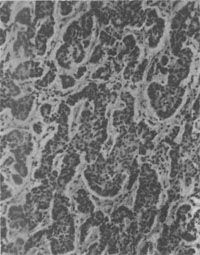

镜下见细胞较小,形态一致,为圆形或多角形,核小而规则。胞浆轻度嗜碱性,有嗜银颗粒,颗粒内含5-羟色胺。细胞形成实体状或索状胞巢,有时可见其中有假菊形团样结构(图10-28)。电镜观察可见细胞浆内有直径100~300nm的球形分泌颗粒,颗粒中有有一电子致密核心,颗粒周边有高电子密度的界膜。常限于粘膜及粘膜下层,少数可达浆膜层。发生在阑尾的类一般恶性度较低,转移率为3%。但发生在其他肠段及其他部位的类,则有约2/3为恶性者,并常转移到肝。

图10-28 结肠类